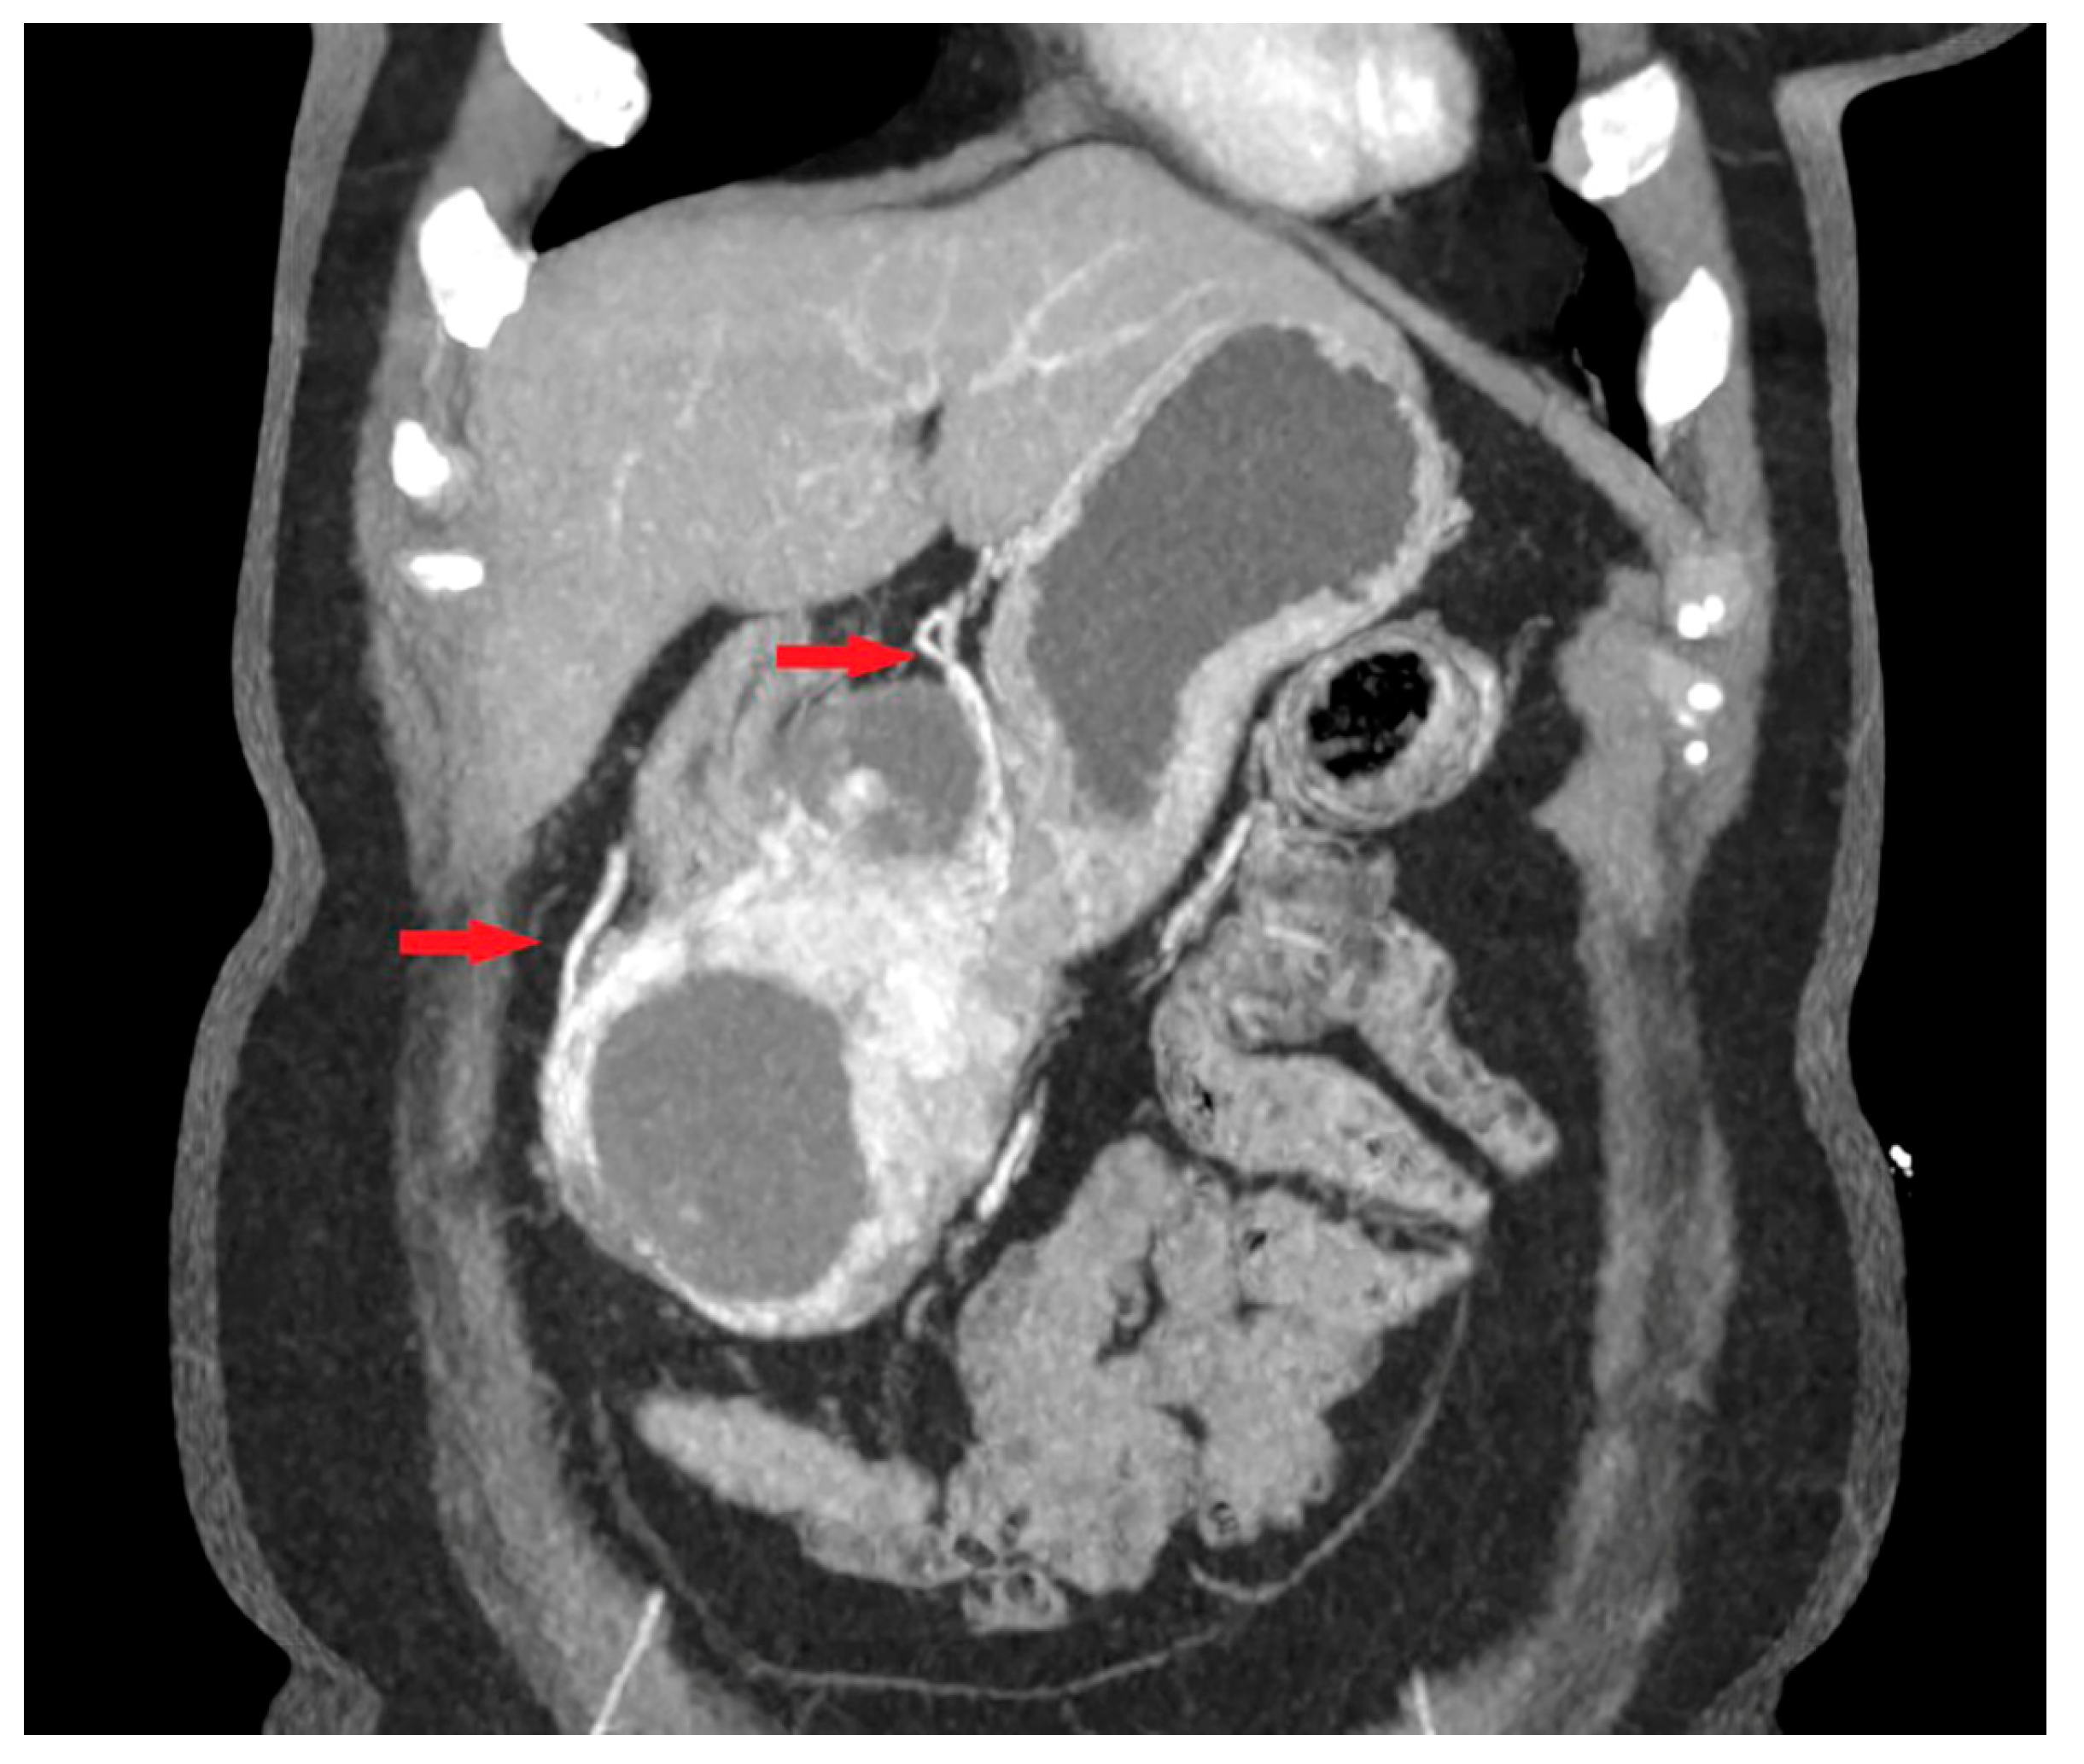

- Maximum diameter: the largest diameter of the tumor in mm (Figure 1);

- Tumor shape: regular or irregular (Figure 1);

- Growth mode: exophytic/mixed and endophytic (Figure 1);

- The presence of visible enlarged vascular structures draining/feeding the tumor (EFDV “enlarged feeding or draining vessel”) (Figure 6);